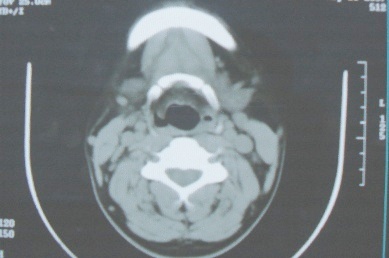

ct10755,男,28岁。发现左侧腮腺区肿块几年,今要求ct检查。左侧腮腺区低密度影,ct值-153hu。

左侧腮腺区囊状低密度影,ct值-153hu,考虑腮腺脂肪瘤。

病灶为一边界清晰脂性区,其内未见实质性组织.支持考虑:左侧腮腺脂肪瘤可能性大.

ct能定性的良性肿瘤不多,对脂肪瘤的诊断是比较有把握的,加大窗宽还可以看到里面有分隔

ct值-153hu,腮腺脂肪瘤。